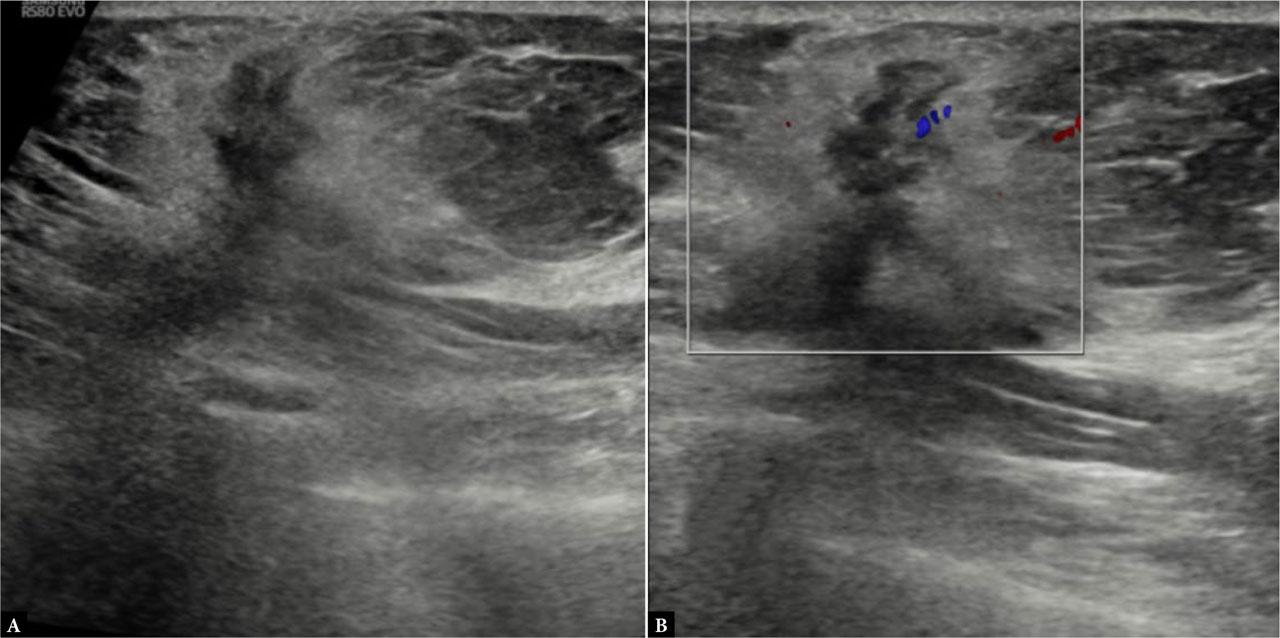

Fig. 1.